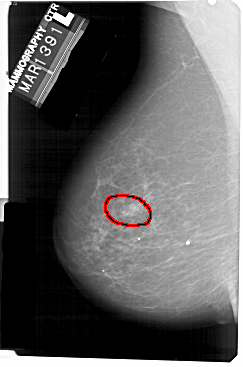

A_1341_1.LEFT_MLO

LEFT_MLO LINES 5491 PIXELS_PER_LINE 3631 BITS_PER_PIXEL 12 RESOLUTION 43.5 OVERLAY

FILE: A_1341_1.LEFT_MLO.OVERLAY

TOTAL_ABNORMALITIES 1

ABNORMALITY 1

LESION_TYPE MASS SHAPE ROUND MARGINS ILL_DEFINED

ASSESSMENT 4

SUBTLETY 4

PATHOLOGY BENIGN

TOTAL_OUTLINES 1

BOUNDARY